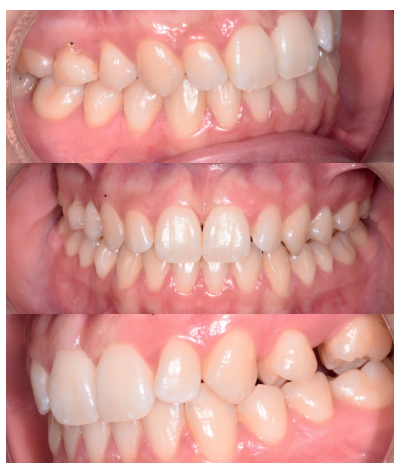

Caso clínico: se presenta un caso clínico de una mujer de 20 años, sin antecedentes médico-quirúrgicos de interés, que acudió a consulta remitida por su ortodoncista, para la extracción de un premolar maxilar retenido, en posición invertida. Tras la extracción del premolar y del tercer molar inferior retenidos, se obtuvo dentina procedente de ambos, para la regeneración ósea guiada del defecto resultante de la extracción del premolar, realizando revisiones a la semana y a los 4 meses de la intervención.

Clinical case: a clinical case of a 20-year-old woman is presented, with no interesting medical record, who went to dental clinic for removal of an inverse maxillary bicuspid retained. After maxillary bicuspid and lower third molar extractions, autogenous dentin was obtained from both teeth, to perform a guided bone regeneration of the bicuspid defect. A week and 4-month check-up were carried out.